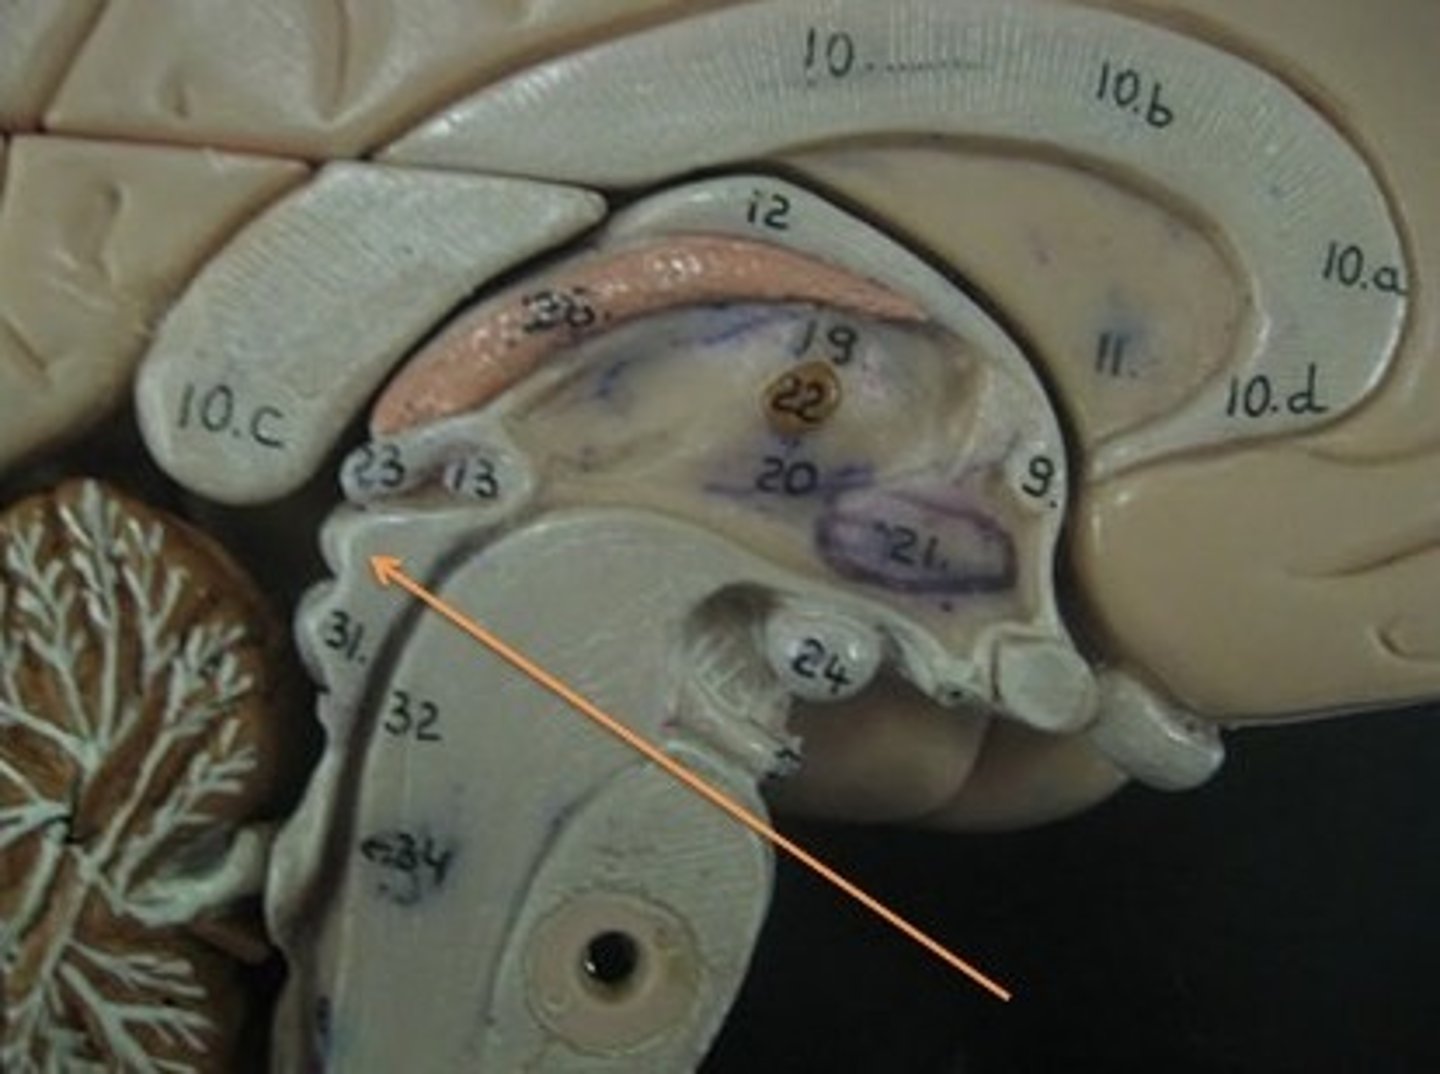

Interthalamic adhesion

Thalamus

Hypothalamus

Mammillary body

Pituitary gland

choroid plexus

cerebral aqueduct

third ventricle

fourth ventricle